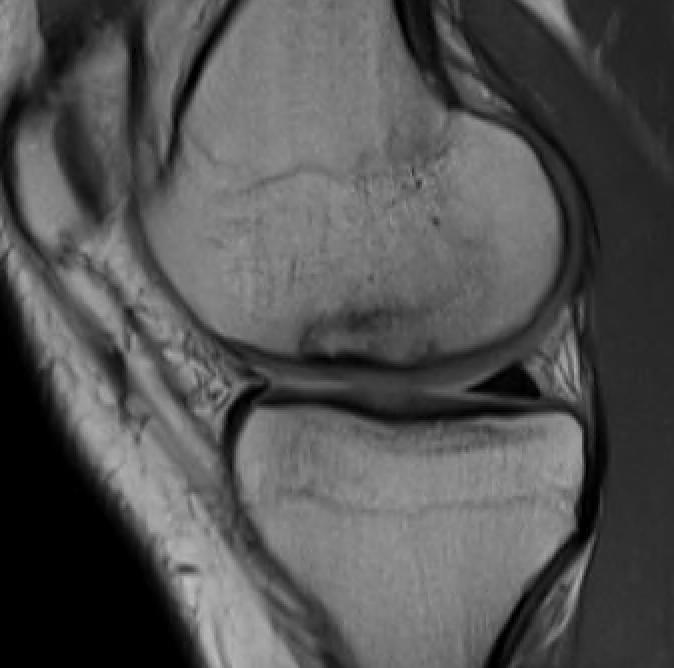

T1 sagittal on presentation T1 sagittal six months later

Progression of reossification over 6 months following drilling